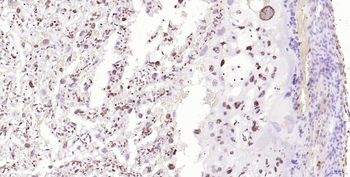

100 μl, 200 μl, 50 μl - RORC Rabbit Polyclonal Antibody [orb6888]Featured

FC, ICC, IF, IHC-Fr, IHC-P, WB

Human, Mouse, Rat

Bovine, Canine, Equine, Gallus, Porcine, Rabbit

Rabbit

Polyclonal

Unconjugated

50 μl, 100 μl, 200 μl - Featured